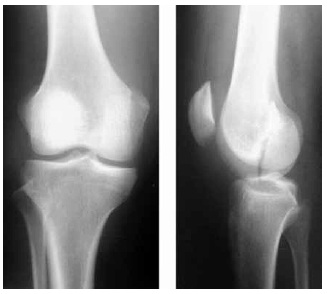

Considere a radiografia:

A fratura do porção distal do fêmur apresentada nessa radiografia é classificada pela AO: